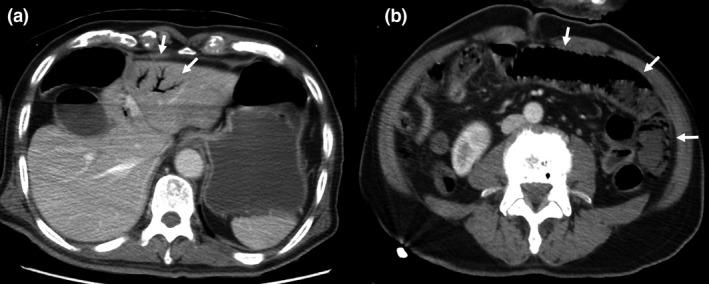

A 77-year-old man was transferred due to shock and disorder of consciousness. He was diagnosed with an HHS. We suspected intestinal ischemia due to a small amount of HPVG revealed by computed tomography (CT). Peritoneal signs were revealed after treatment for the HHS. Computed tomography was carried out again 5 h after admission, which showed a large amount of HPVG, remarkable bowel dilatation, and pneumatosis intestinalis. We performed an emergency laparotomy and resected the small bowel necrosis resulting from NOMI.

一名77岁男性因休克和意识障碍被转诊。他被诊断为HHS。由于计算机断层扫描(CT)显示少量HPVG,我们怀疑存在肠道缺血。在对HHS进行治疗后出现了腹膜刺激征。入院5小时后再次进行CT检查,结果显示大量HPVG、明显的肠扩张和肠壁积气。我们进行了急诊剖腹手术,切除了由NOMI导致的小肠坏死。